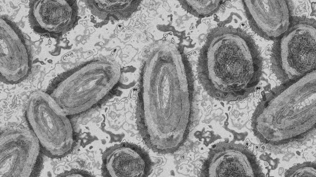

Fransa'da maymun çiçeği alarmı! Yeni varyant tespit edildi

Almanya'da özel bir okulda 2 maymun çiçeği virüsü tespit edildi

Dünya Sağlık Örgütüne göre maymun çiçeği halk sağlığı acil durumu oluşturmaya devam ediyor

Afrika'da maymun çiçeği vakaları hızla artıyor: Son bir haftada 50 kişi öldü

DSÖ'den korkutan maymun çiçeği virüsü açıklaması: Daha hızlı yayılıyor

DSÖ: Dünya genelinde 90 binden fazla maymun çiçeği virüsü vakası görüldü

Maymun çiçeği virüsü 92 ülkede görüldü: Dünya genelindeki vaka sayısı 35 bini aştı

DSÖ, maymun çiçeği varyantlarına yeni isim verdi

Maymun çiçeği vakalarında artış! DSÖ 'acil durum' ilan etti